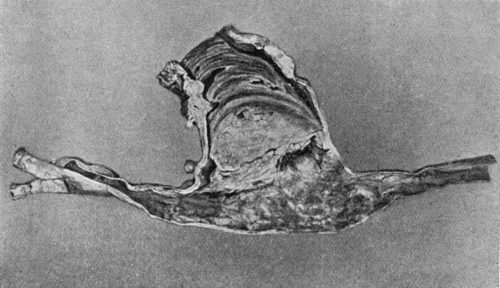

| 84. | Stump Neuromas of Sciatic Nerve | 345 |

| 85. | Stump Neuromas, showing changes at ends of divided Nerves | 354 |